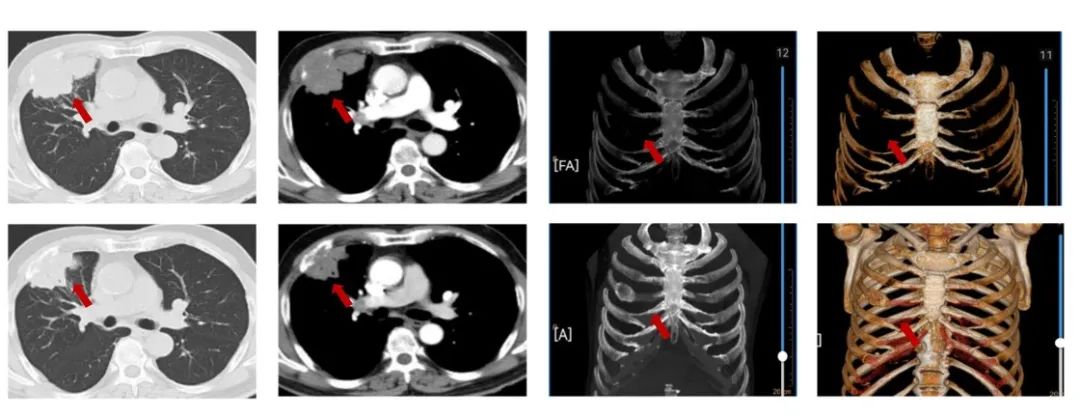

患者刘XX,男,65岁,2021年6月以“右胸痛2个月”为主诉入院,NRS7分,PS1分,吸烟30年,每天20支。外院胸部ct提示:右肺上叶团块影,PET/CT提示:右肺上叶前段可见不规则软组织肿块,范围约68mmx47mm,SUVmax=16.7,病变侵犯胸壁及右侧第4前肋;右肺上叶另见肿块及小结节,葡萄糖代谢增高。纵隔4R淋巴结代谢略增高,右肺上叶前段肺内转移;右肺门淋巴结代谢略增高,SUVmax=3.7,纵隔4R及右肺门淋巴结转移可能性大,未见胸膜增厚及胸腔积液,肝内钙化灶;气管镜取得病理,结合免疫组化为鳞状细胞癌,PD-L1(22C3)CPS=15。cT3N2M0 IIIB期,经MDT讨论后,为潜在可切除者先行免疫联合化疗,进行转化治疗,替雷利珠单抗+白蛋白紫杉醇/卡铂治疗3周期治疗,评效为缩小的SD。NRS 2分。

图1:由上至下分别展示基线(A.)及免疫化学治疗后改变(B.)。红色箭头指示病灶位置,由左至右分别为右肺肿物肺窗、右肺肿物纵隔窗、肋骨三维重建。